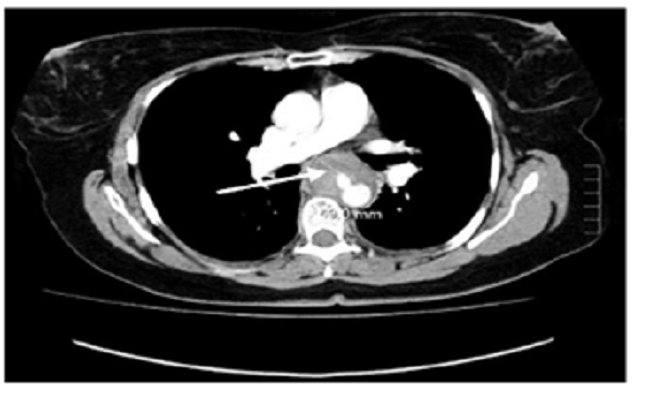

En la revisión de la angiotomografía, se encontraron signos sugestivos de ruptura contenida de la pared lateral derecha de la aorta torácica a nivel de la carina, con engrosamiento de las paredes del esófago proximal y pequeño derrame pleural libre bilateral (figura 1).